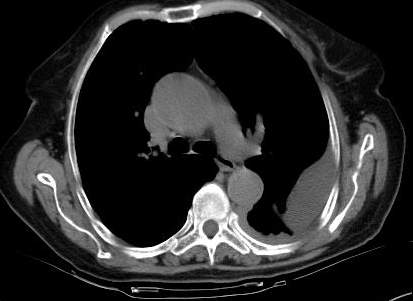

标题: CT0563:病历讨论,胸膜间皮瘤?

测ct值3-6hu,

既然ct值是3-6hu,还不如考虑包裹性积液。

请上传纵隔窗。目前还是支技包裹性积液(明显梭形),即使是间皮瘤并积液也少梭形的。

从图片看,包裹性积液好象更合理,梭形,ct值3-5hu(在哪看到的?);胸膜间皮瘤如此规则,不多见。

左侧背部胸膜肥厚,伴包裹性积液,不考虑间皮瘤.

同意以上各位的高见,首先考虑包裹性积液,1.胸膜间皮瘤积液量一般较大,以游离性积液更为常见,2.可以看到增厚的胸膜结节